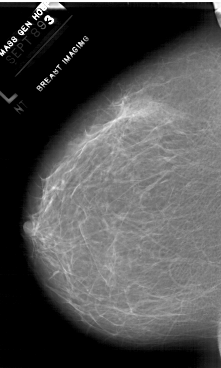

A_1717_1.LEFT_CC

LEFT_CC LINES 6616 PIXELS_PER_LINE 3976 BITS_PER_PIXEL 12 RESOLUTION 43.5 NON_OVERLAY